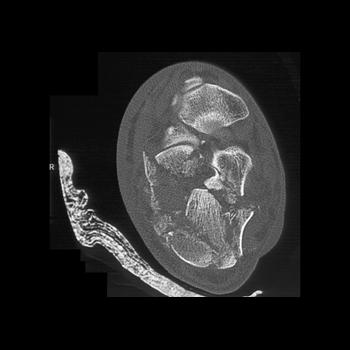

Foot Pathology: Calcaneal fractures

The calcaneus is the most commonly fractured tarsal bone. Calcaneal fractures are classified as intraarticular and extraarticular. The intraarticular fracturesaccount for 70-75% of calcaneal fractures and carry a worse prognosis. The inciting trauma is usually a fall or motor vehicle accident, and these fractures are bilateral in 10% of cases. Concomitant ipsilateral lower extremity fractures are present in 20-46% of cases, and spinal fractures in 10-30%. Extrarticular fractures (Figure: extraarticular fracture of calcaneus) account for 25-30% of calcaneal fractures, and are the sequela of a twisting injury. Anatomic regions affected include the anterior or medial process, the sustentaculum tali, the body or the tuberosity. Severe fractures are readily evident on conventional radiographs; however, CT is essential for elucidating the extent of injury. The intraarticulur fractures are often comminuted and may be displaced. CT is also used for follow up after fracture treatment. CT is very helpful for detecting fracture malunion or nonunion . In addition, the presence and extent of secondary osteoarthritis is readily detected by CT. Several features of intraarticular fractures which can be elucidated on CT have been shown to correlate with the outcome. A central depression fracture has a worse prognosis than a tongue-type fractures, but a better prognosis than a comminuted fracture. An unsatisfactory result is more likely in the setting of subtalar incongruity, decreased fibulocalcaneal space and osteoarthrosis of the talonavicular joint and the ankle.